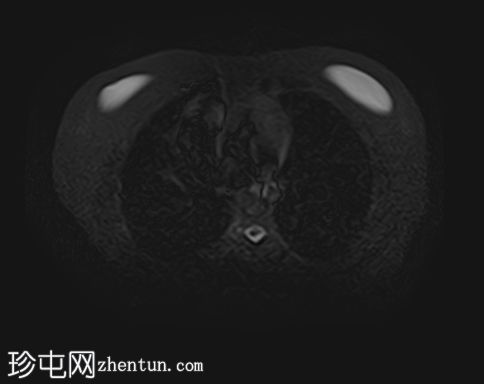

MRI

轴位T2加权像

STIR(FASE)序列

轴位

T2加权像

左侧肾上腺可见一边界清晰的病灶,大小约为3.0 × 2.4 × 2.0 cm。

化学位移成像显示,反相图像的信号强度较同相图像明显降低,与细胞内脂质含量相符。

右肾先天性缺失。左肾轻度肥大,信号强度正常。

肾上腺腺瘤的典型表现,反相成像可见明显的信号丢失。